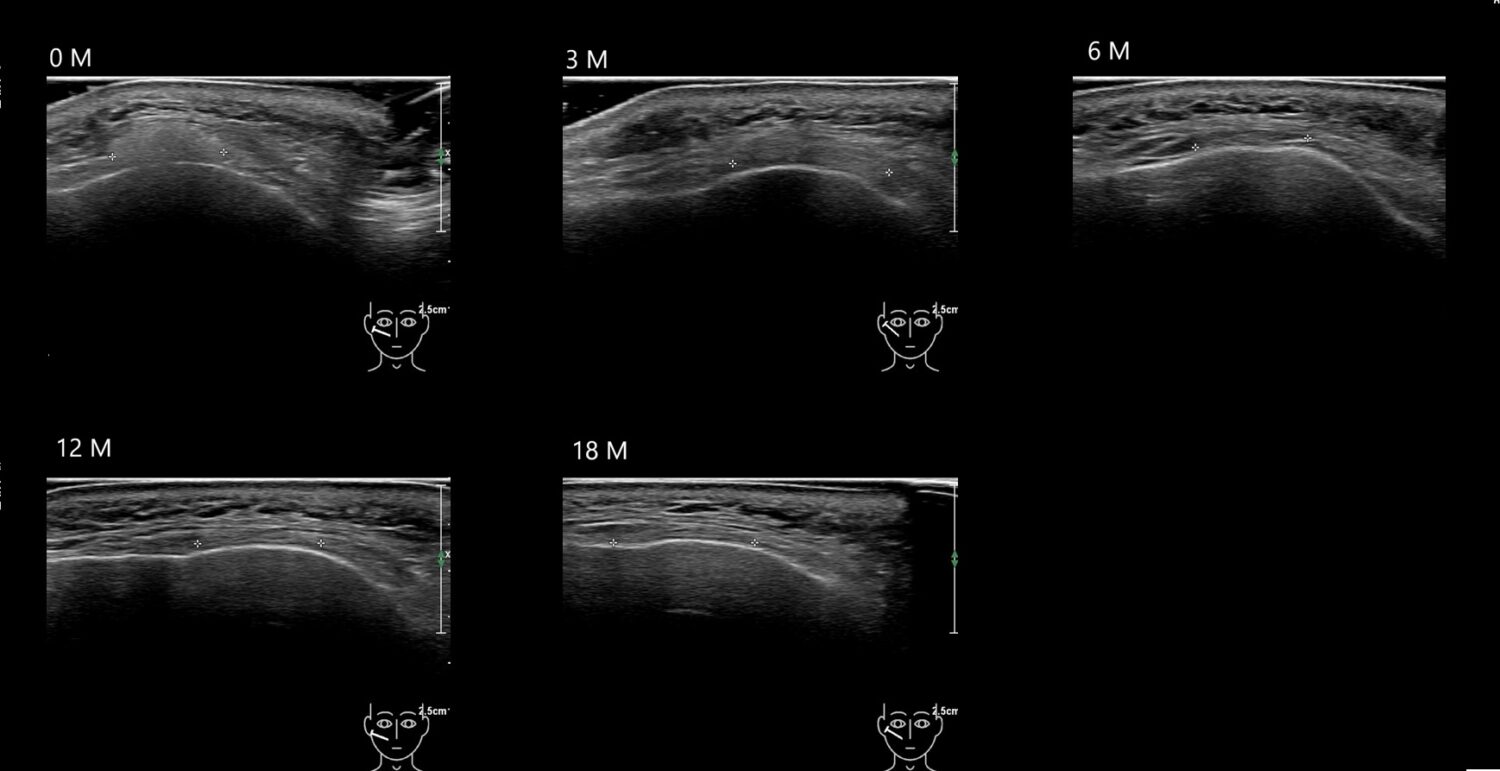

Fillers

Draw in the second image below where the fillers are located. To check if your answer is correct, swipe the first image to the right.